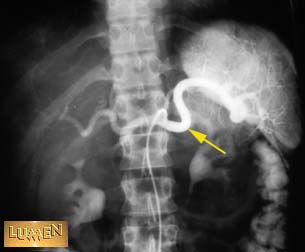

Question: Identify.

Splenic artery.